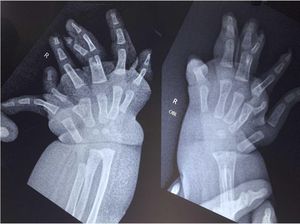

Bayi di Aceh Punya 10 Jari Kaki, Begini Penampakannya

Seorang bayi di Aceh mengalami kondisi medis yang langka karena memiliki 10 jari di kaki kirinya. Kasus ini dipublikasikan dalam sebuah jurnal.